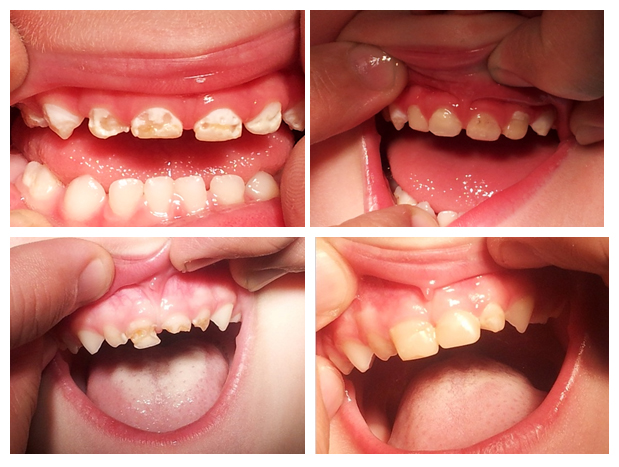

Najtragičnije je što se razvoj karijesa kod beba i male dece može lako sprečiti, a u početnim stadijumima bolesti zub se može u potpunosti oporaviti. Zbog toga je izuzetno značajno da pedijatri, a pogotovu roditelji prepoznaju prve znake(Slika 2). To će moći jedino ako posmatraju zube svojoj deci i ako se obuče za to.

Bele mrlje, koje su prvi znaci zubnog kvara, treba razlikovati od urođenih defekata u razvoju zubne gledji. Bele mrlje se uvek nalaze uz desni, koje često krvare na dodir. Urođeni promene, bilo u obliki mrlja(hipomaturacija) ili defekata(hipoplazija) postoje i na tek izniklim zubima i smešteni su dalje od desni.(Slika 2.)

Slika 2. Prvi znaci karijesa ranog detinjstva su tzv. bele mrlja u predelu ruba desni. One su znak topljenja gleđi. U poroznu gleđ belih mrlje mogu da uđu pigmenti kada dobija izgled braon mrlja. Bele mrlje kao prev znake karijesa treba razlikovati od urođenih defekata gleđi.

Ukoliko se na vreme ne reaguje na mestima belih mrlja zubna gleđ puca i stvaraju se defekti.(slike 3 i 4) Oni mogu veoma brzo da se šire i da u roku od nekoliko nedelja dođe do preloma kompletnog zuba(slika 1).

Slika 3. Različiti stadijumi karijesa kod beba i način njihovog zbrinjavanja. Strelice pokazuju razaranja zubne gledji na unutrašnjim površinama usled noćnog dojenja i korišćenja bočice sa mlekom ili sokom.